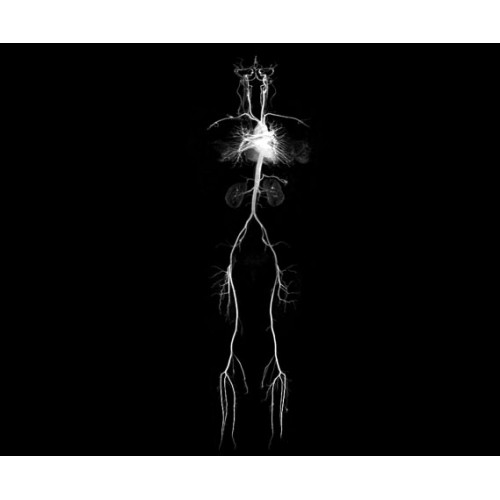

• CVWorks — приложения для кардио-визуализации помогут получить данные о морфологии, динамике кровотока, функции миокарда, а также информацию о структуре сосудов и динамике кровотока.

МР-ангиография

Да